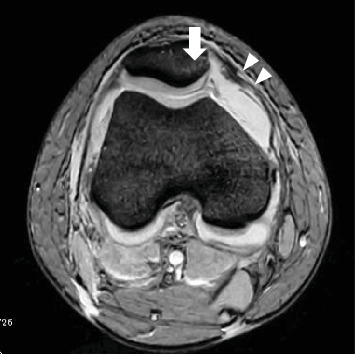

一个健康的16岁女孩在髌骨脱位后出现股骨外侧髁(LFC)后侧骨软骨骨折。骨软骨碎片固定及髌股内侧韧带重建均取得满意效果。据我们所知,这只是第三例报道的后LFC骨软骨骨折病例。然而,我们认为损伤机制与前两个病例不同。

A healthy 16-year-old girl presented with an osteochondral fracture of the posterior aspect of the lateral femoral condyle (LFC) following patellar dislocation. Satisfactory results were obtained with osteochondral fragment fixation and medial patellofemoral ligament (MPFL) reconstruction. To the best of our knowledge, this is only the third reported case of an osteochondral fracture of the posterior LFC. However, we believe that the mechanism of injury differed from that in the two previous cases.